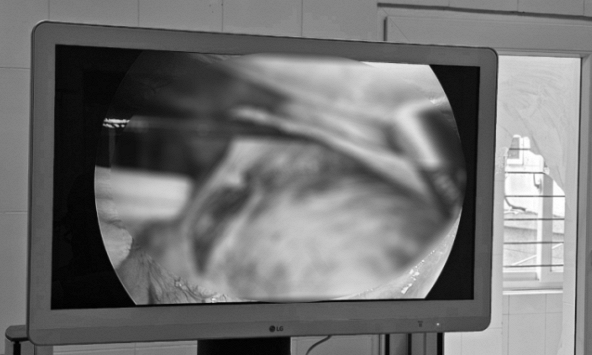

Đau tức hông lưng, nội soi người đàn ông thấy nhiều thứ này "bao vây, chèn ép" 2 quả thận